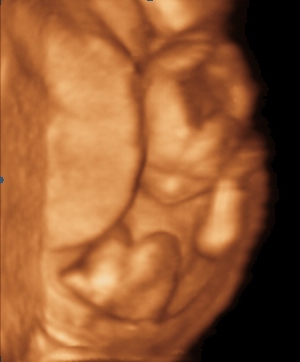

vazime 84g a sme 14+3. pohlavie neprezradil, ideme na utz 23.10 a vraj tam nam to povie, ale dal nam videjko napalene a ja tam vidim ked sa babo mrvi nieco vysiet take male gulate xixi

@atreyu To sú lebečné kosti, oni sa len postupne vytvárajú a približujú k sebe 😉 Sama som zvedavá, či mi doki bude robiť v pondelok v poradni sono, ale u Teba je to podľa mňa isté. Ja som sa bála vaginálnych ultrazvukov, ale krátky ultrazvuk cez bruško nemôže uškodiť. A zvlášť keď Ťa bolí bruško, určite si ho vyžiadaj, budeš potom oveľa kľudnejšia 😉